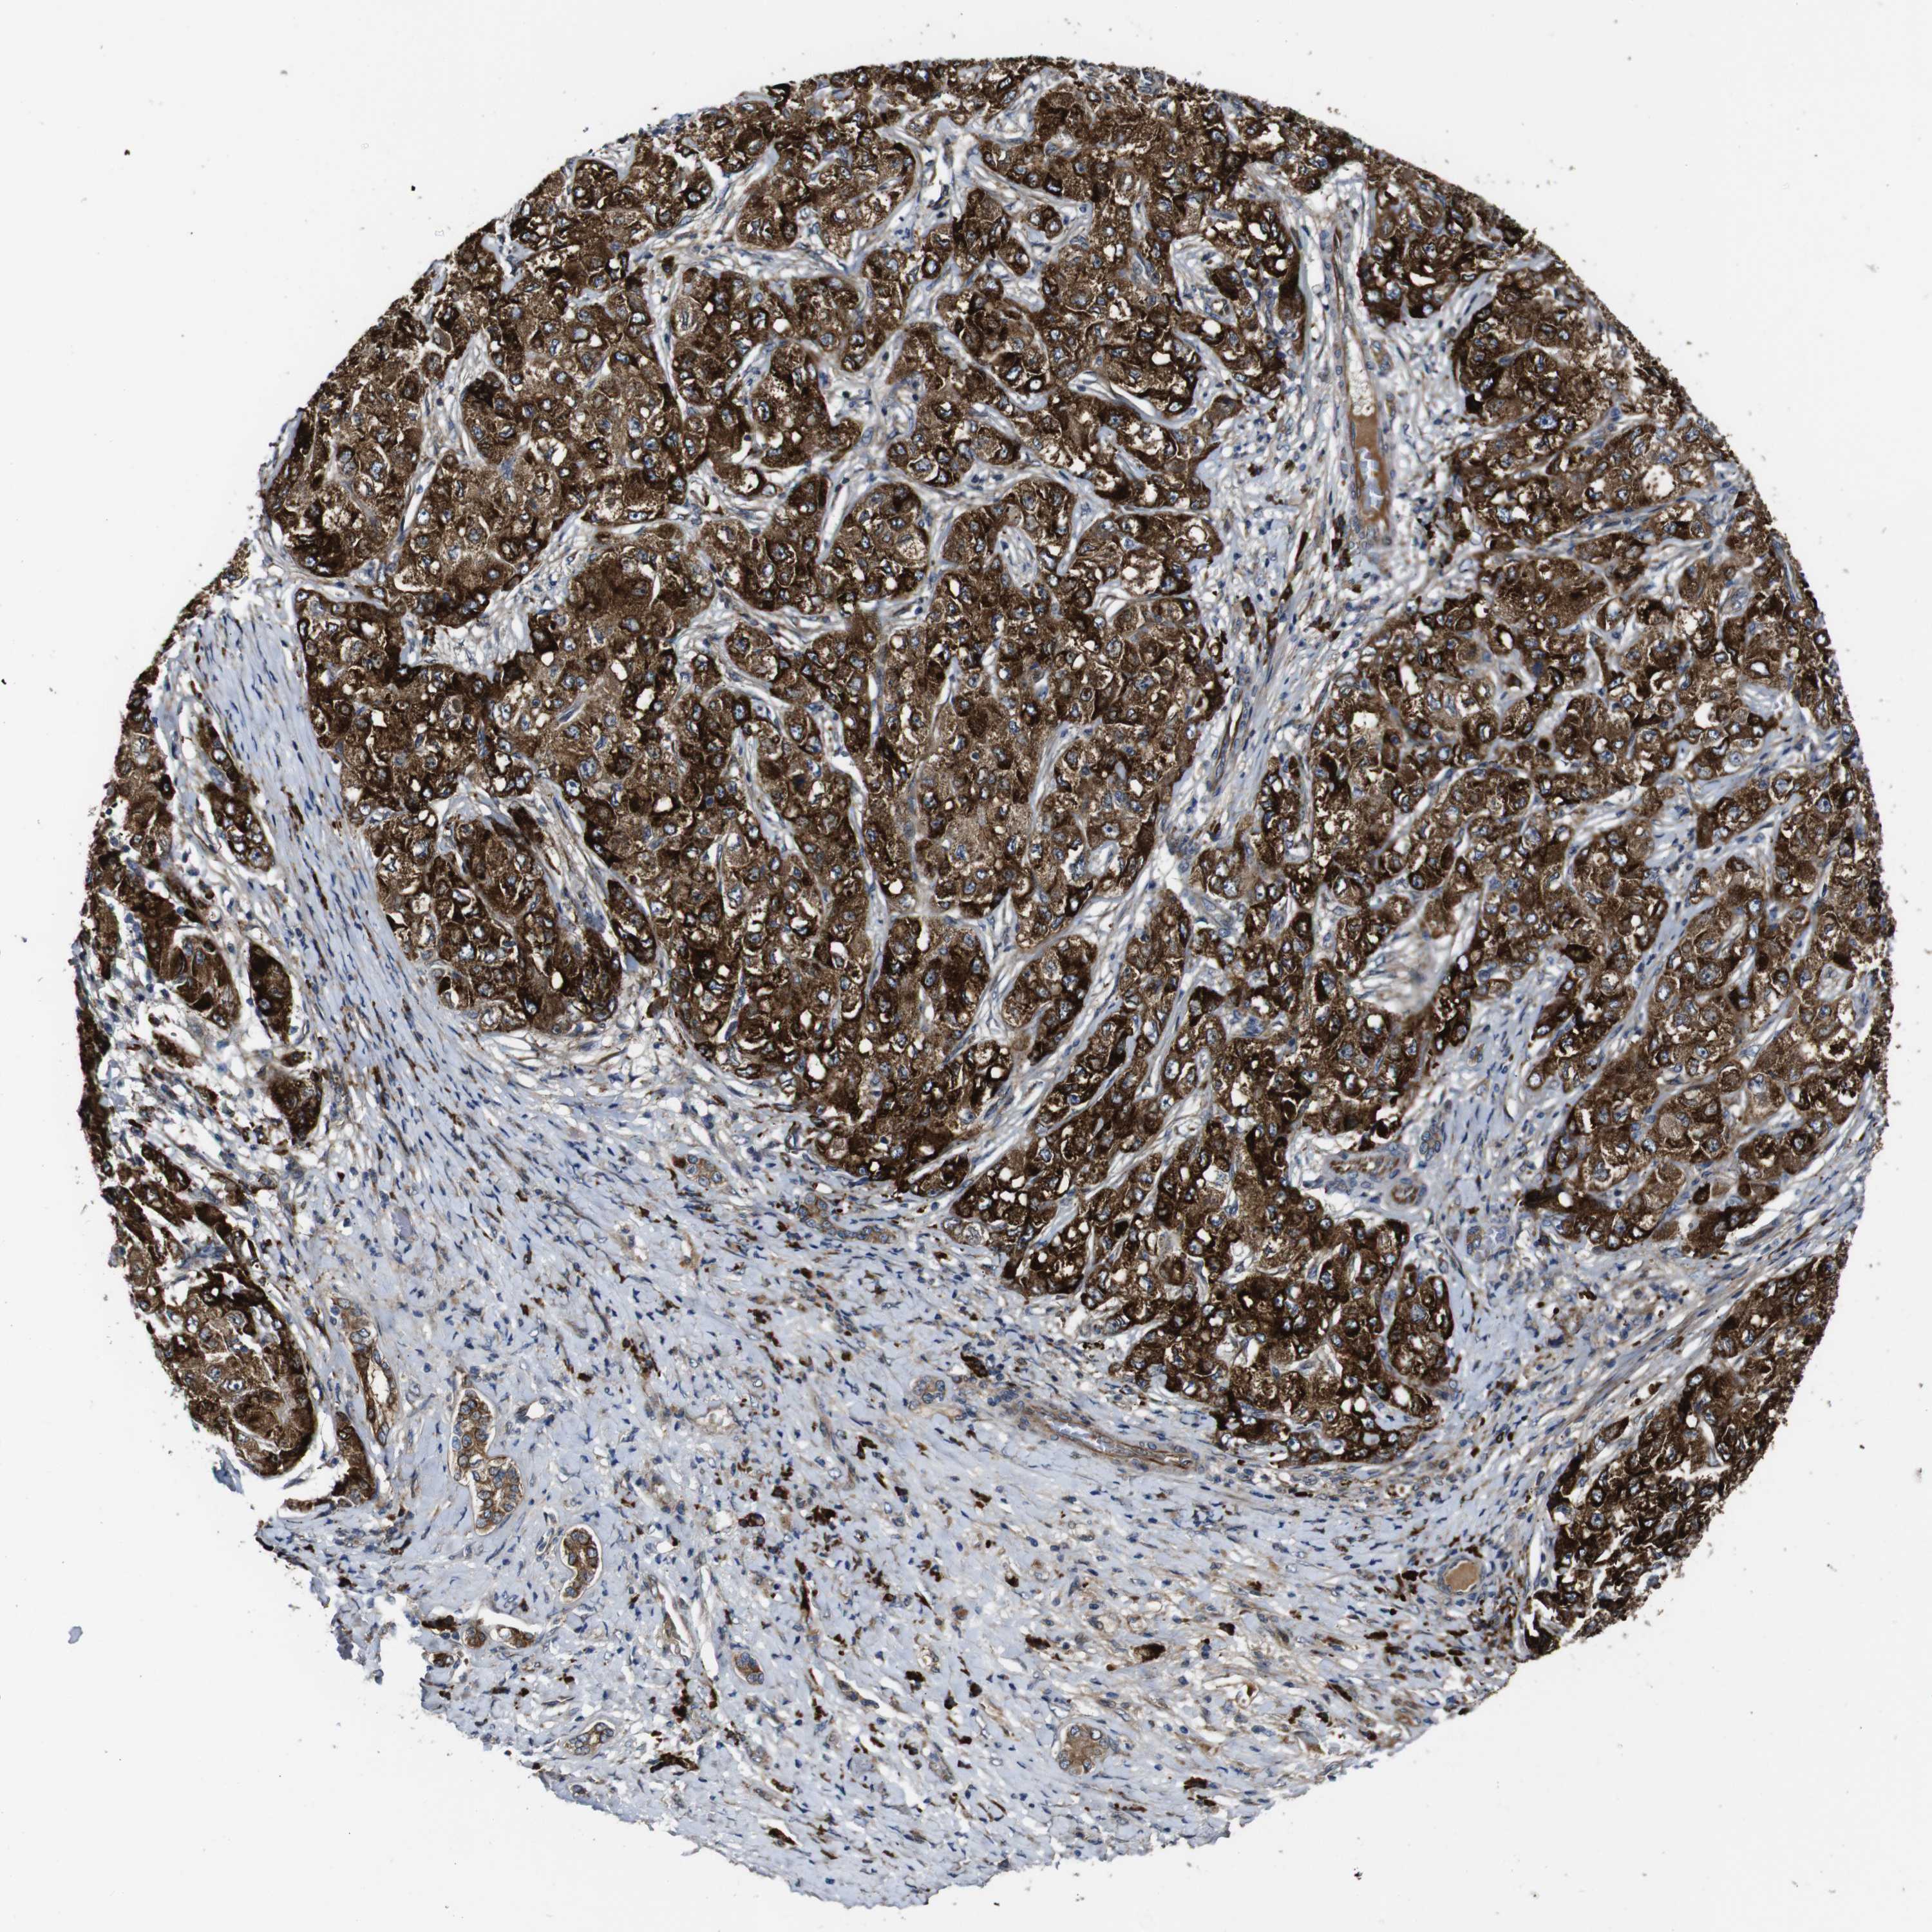

LIVER CANCER - Protein expressioni

A mouse-over function shows sample information and annotation data. Click on an image to view it in a full screen mode. Samples can be filtered based on level of antibody staining by selecting one or several of the following categories: high, medium, low and not detected. The assay and annotation is described here.

Note that samples used for immunohistochemistry by the Human Protein Atlas do not correspond to samples in the TCGA dataset.

Antibody stainingi

Antibody staining in the annotated cell types in the current human tissue is reported as not detected, low, medium, or high, based on conventional immunohistochemistry profiling in selected tissues. This score is based on the combination of the staining intensity and fraction of stained cells.

Each image is clickable and will lead to virtual microscopy that enables deeper exploration of all samples and also displays staining intensity scores, fraction scores and subcellular localization as well as patient and tissue information for each sample.

Antibody HPA003332

Staining

High

Medium

Low

Not detected

Intensity

Strong

Moderate

Weak

Negative

Quantity

>75%

75%-25%

<25%

None

Location

Nuclear

Cytoplasmic/membranous

Cytoplasmic/membranous,nuclear

Cholangiocarcinoma

Carcinoma, Hepatocellular, NOS